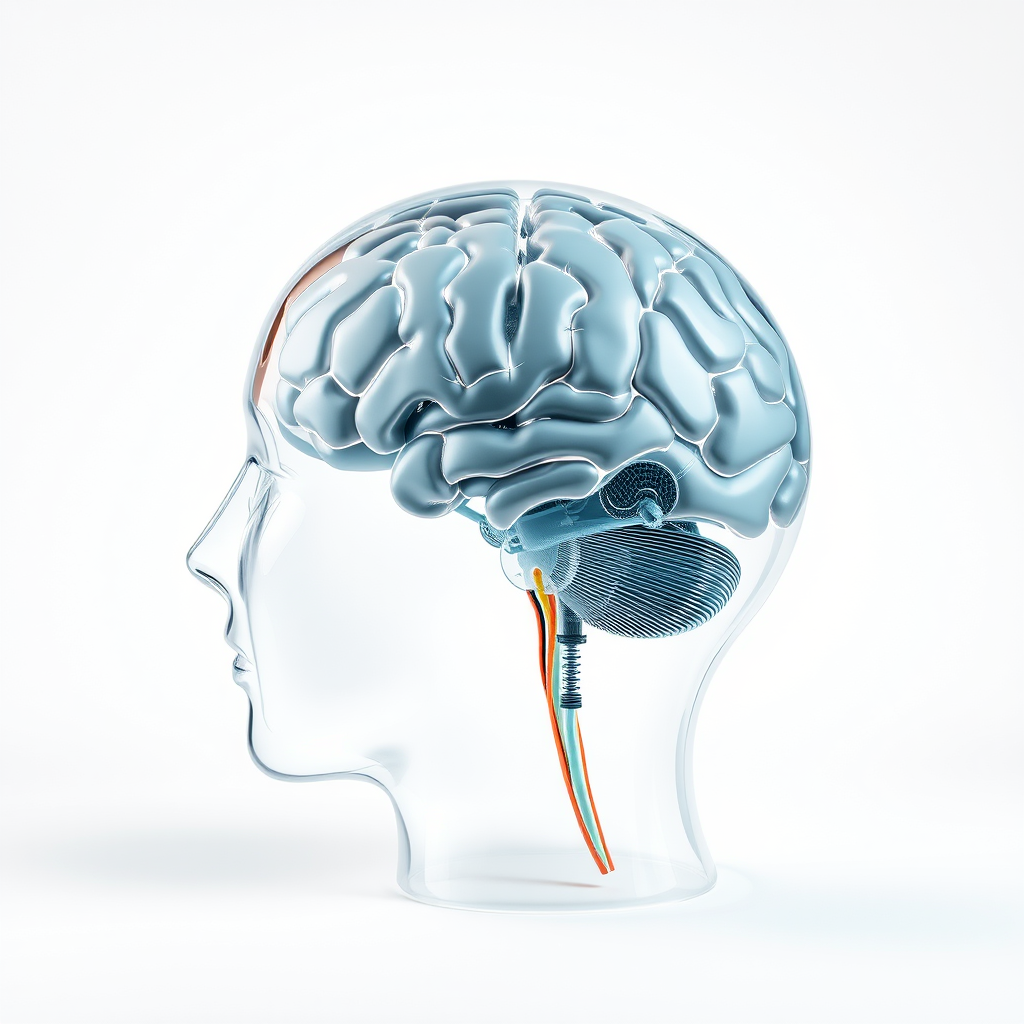

Técnicas de Reabilitação Neuropsicológica

Técnicas de reabilitação neuropsicológica são fundamentais para a recuperação de funções cognitivas em indivíduos que enfrentam desafios mentais e comportamentais.

A reabilitação neuropsicológica é um processo que envolve diversas etapas e métodos, todos focados na restauração das capacidades cognitivas e comportamentais.

Abordagens e Técnicas Utilizadas

Intervenções Personalizadas

Essas atividades são projetadas para estimular as áreas do cérebro que precisam de reabilitação, ajudando os pacientes a recuperar suas capacidades cognitivas e a melhorar sua qualidade de vida.

O Compromisso com a Excelência

Com um compromisso sólido com a excelência, a empresa investe continuamente em formação e atualização de seus profissionais.

Isso promove que as técnicas de reabilitação neuropsicológica utilizadas estejam sempre alinhadas com as melhores práticas do setor.